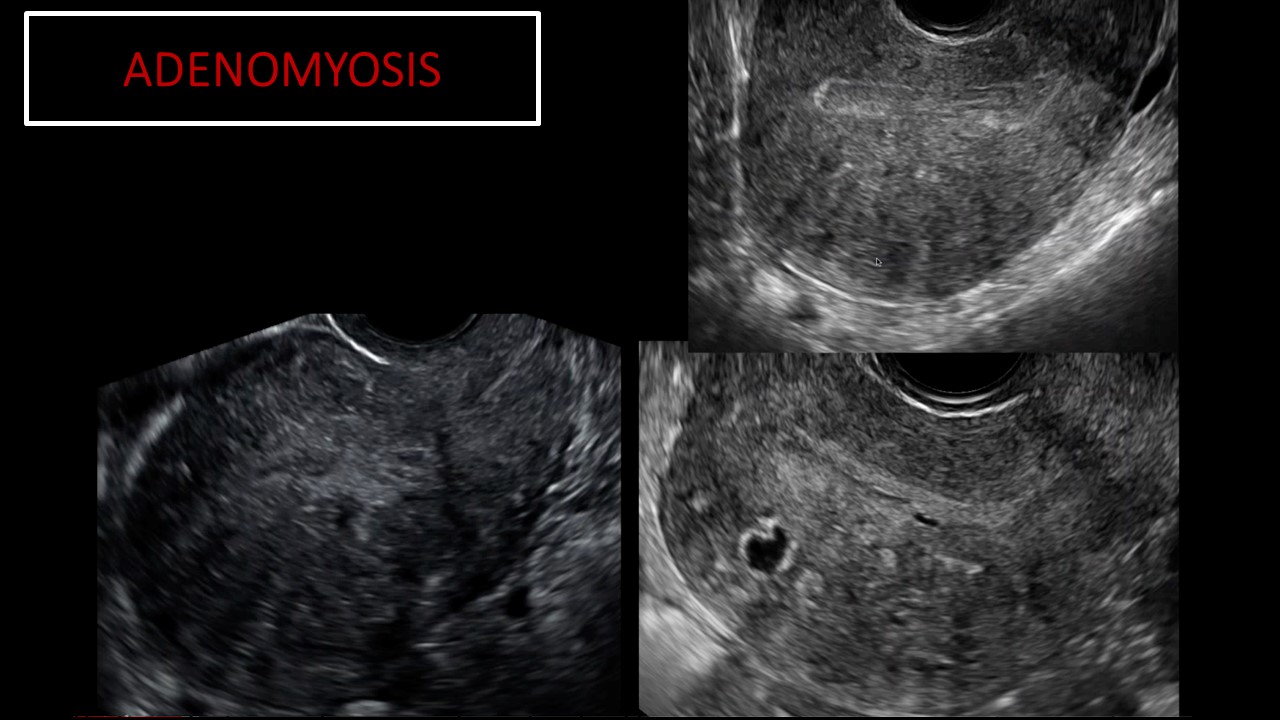

Vai trò của siêu âm trong chẩn đoán và điều trị hiếm muộn

Từ khóa: Vai trò của siêu âm trong chẩn đoán và điều trị hiếm muộn